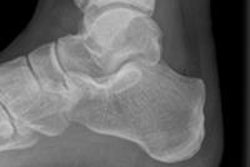

In professional football players, overuse injuries in the ankle are particularly common, according to Dr. Patricia Cunningham, a radiologist from Louth-Meath Hospital Group in Ireland. She said it's important to diagnose injuries of the ankle ligaments, including sequelae such as anterolateral impingement, as well as injuries of tendons around the ankle and bone and cartilage injuries in the ankle, including anterior and posterior impingement.